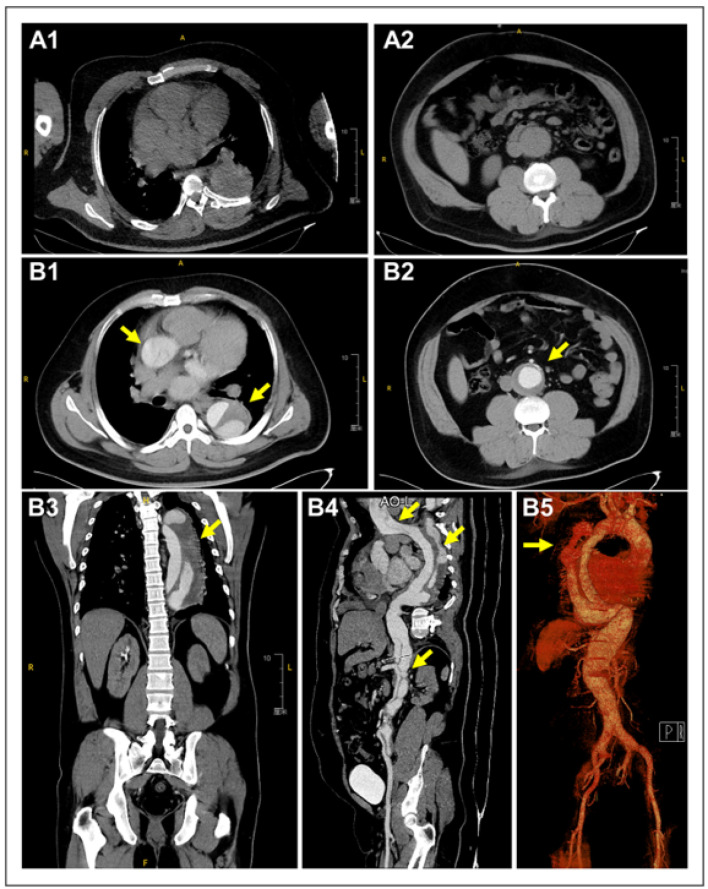

主动脉夹层(Aortic dissection, AD)是一种危及生命的心血管急症,其特征是由于内膜撕裂导致主动脉内层和中间层分离。根据撕裂的位置和程度将其分为斯坦福A型或B型。症状各不相同,但通常包括胸部、背部或腹部的剧烈疼痛,并伴有非典型症状,如休克、心力衰竭或晕厥。终末器官缺血,包括中风和肢体坏死,可能发生。及时诊断和干预对生存至关重要。在这里,我们报告了一位31岁的男性患者,他表现出急性神经系统症状,最初怀疑有中风,但最终通过计算机断层扫描(CT)血管造影诊断为斯坦福a型AD。本病例强调了在神经系统症状患者鉴别诊断中考虑AD的重要性,以获得准确和及时的治疗。

Aortic dissection (AD), a life-threatening cardiovascular emergency, is characterized by the separation of the aorta's inner and middle layers due to a tear in the intima. It is classified as Stanford type A or B based on the tear's location and extent. Symptoms vary but commonly include severe pain in the chest, back, or abdomen, along with atypical presentations such as shock, heart failure, or syncope. End-organ ischemia, including stroke and limb necrosis, may occur. Timely diagnosis and intervention are crucial for survival. Here, we report a 31-year-old male patient who presented with acute neurological symptoms, initially suspected of having a stroke, but was ultimately diagnosed with Stanford type A AD upon computed tomography (CT) angiography. This case underscores the importance of considering AD in the differential diagnosis of patients with neurological symptoms for accurate and prompt management.